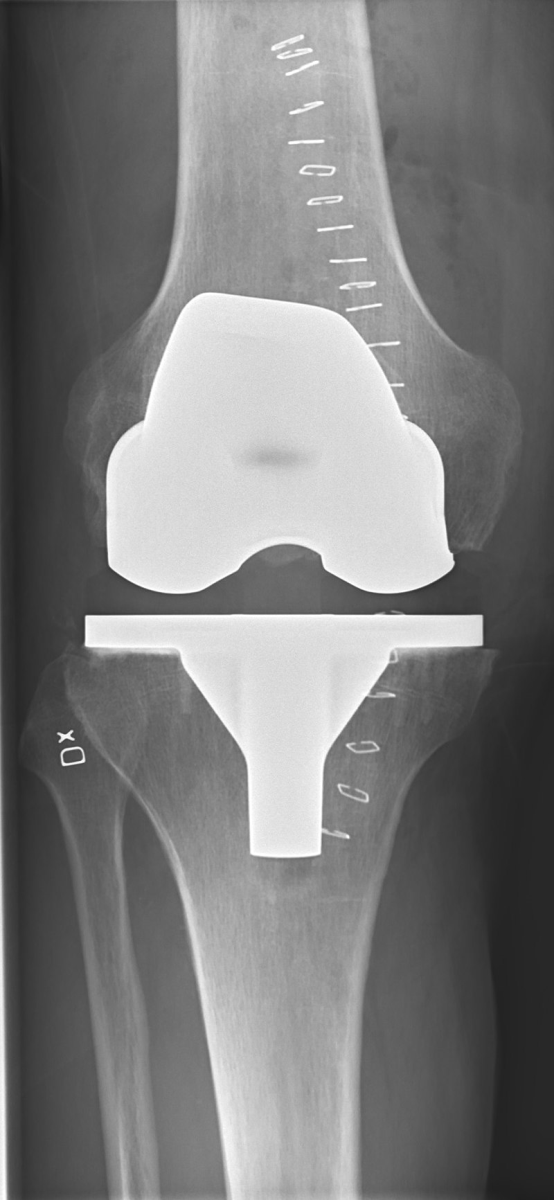

Bilateral gonartrozlu hasta grafisi

Dizin iç kısmında kıkırdak incelmiş ve buna bağlı olarak eklem aralığı daralmış.